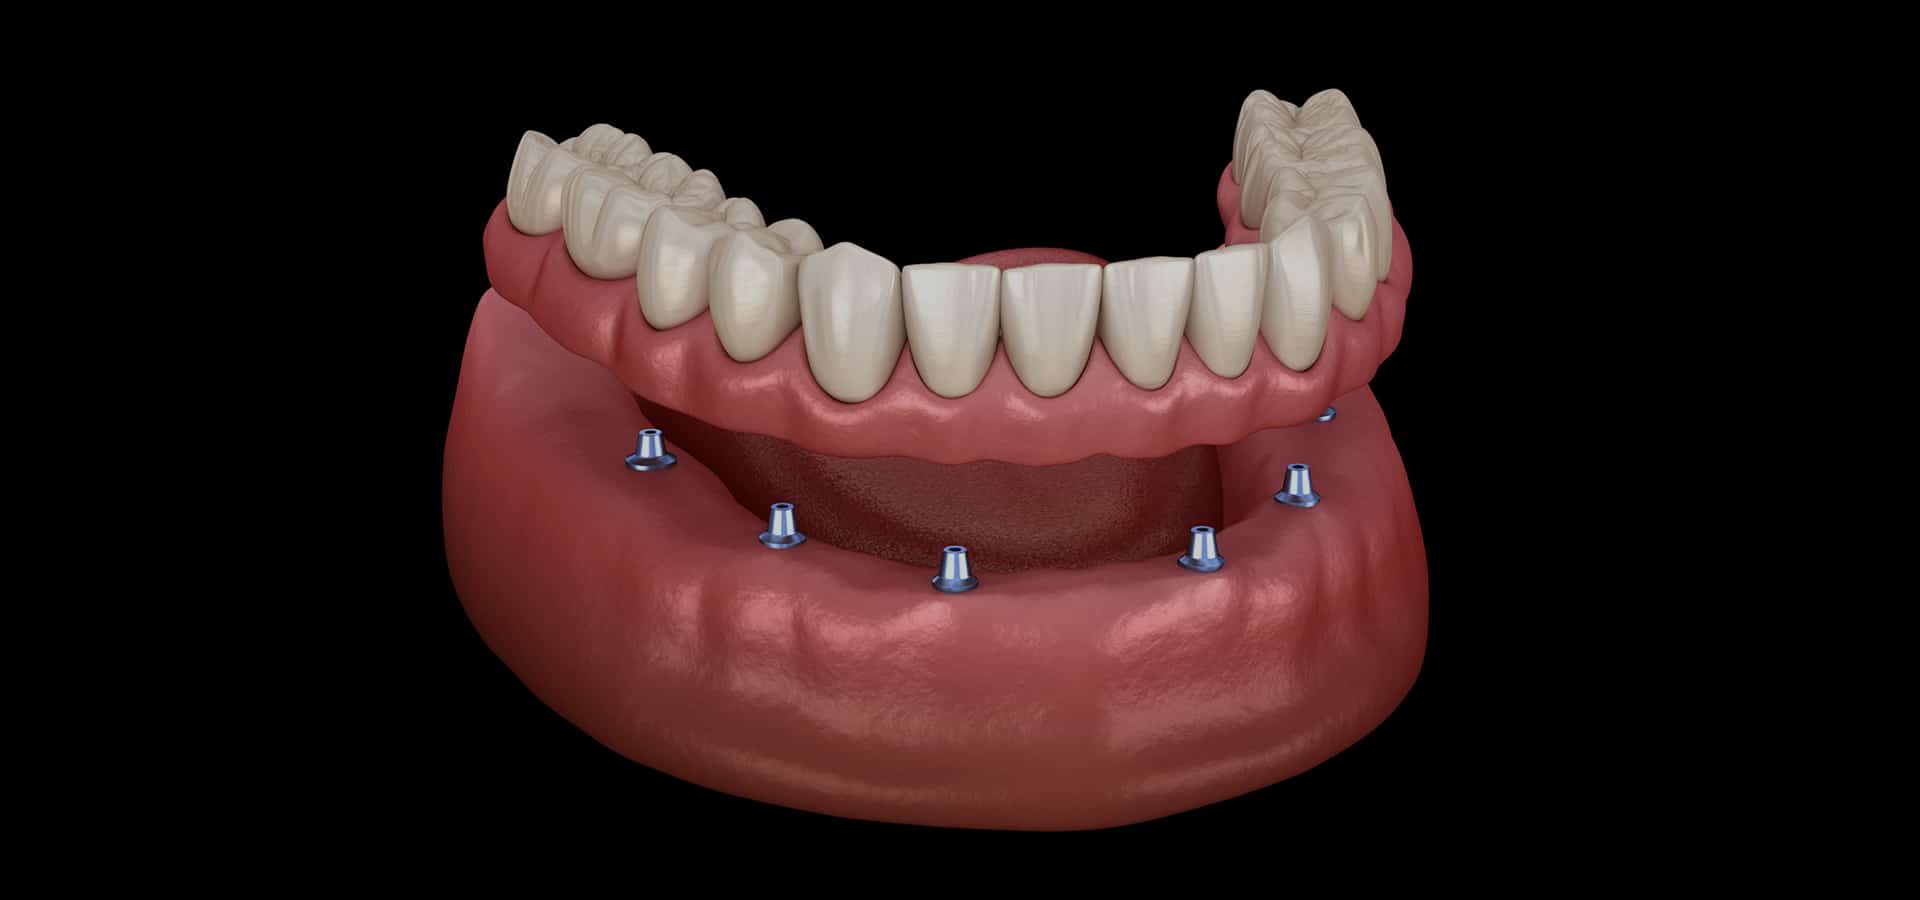

When a tooth is missing, the surrounding bone can begin to resorb, leading to a decrease in both height and width. This resorption can also impact the gum tissue above, resulting in a loss of volume and the natural shape of the area. Following a tooth extraction, this loss of bone and gum tissue can cause functional and aesthetic issues, creating a collapsed appearance.

Dr. Sista at Dentiq Dentistry Houston focuses on proactively preserving tissue. Advances in grafting procedures and bioengineering have made it possible to significantly reduce or eliminate bone and gum tissue loss after tooth extractions. For example, a specially bioengineered dental bone graft material can be placed in the extraction socket after a tooth is removed. This material helps promote new bone growth and has been shown to maintain bone and soft tissue following tooth extraction.

For individuals looking to add implants to their mouths but lacking sufficient bone for safe and secure installation, bone grafting is the ideal solution.